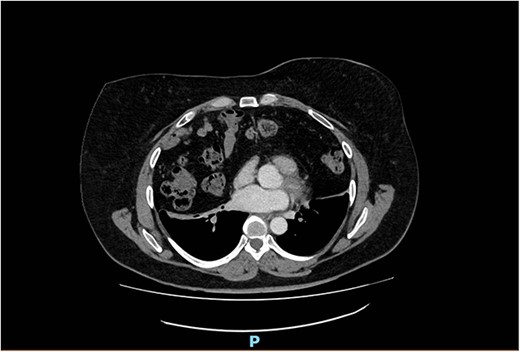

Arterial contrast CT of the chest. Axial slice at the T4/5 level showing herniation of large bowel, small bowel and omentum into the chest cavity. The defect in the anterior diaphragm measures 88.2 mm × 48.2 mm. Of note is the significant reduction in the size of the lung fields.